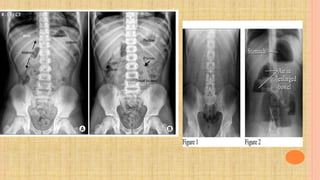

3. Radiography : Plain abdominal radiography reveals signs that suggest intussusception

in only 60% of cases

 Plain radiograph findings may be normal early in the course of intussusception.As

the disease progresses, the earliest radiographic evidence includes an absence of

air in the right lower and upper quadrants and a right upper quadrant soft tissue

density present in 25-60% of patients.

 These findings are followed by an obvious pattern of small bowel obstruction, with

dilatation and air-fluid levels in the small bowel only.

 If the distention is generalized and the air-fluid levels are also present in the colon,

the findings more likely represent acute gastroenteritis than intussusception.???!!! Ask

surgeon !

Acute abdomen series in a child with intussusception

provides the picture of multiple dilated intestinal loops with

step-ladder pattern of air fluid leve